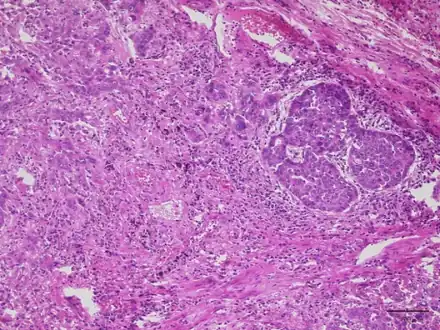

Lung adenocarcinoma with Lambert Eaton myasthenic syndrome-lesion shows proliferation of infiltrating atypical epithelial cells with cribriform or papillary structures -